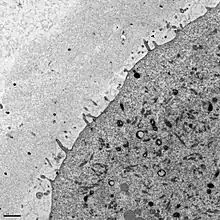

La zone pellucide est une matrice extra-cellulaire glycoprotéique sulfatée qui entoure l’ovocyte. Elle est sécrétée par l’ovocyte I au stade du follicule pré-antral et les cellules péri-ovocytaires de la corona radiata.

Plusieurs types de glycoprotéines sulfatées s’associent pour former un maillage : ZP2 et ZP3 forment des filaments, et ZP1 les relie entre eux. Il existe un 4ème type, les ZP4, mais on n’en connaît pour l’instant pas le rôle[1].

La zone pellucide est essentielle à la survie de l’ovocyte et à la fécondation, elle permet de sélectionner les spermatozoïdes dont la membrane plasmique est intacte et empêche la fécondation croisée (inter espèces). Elle facilite également la migration tubaire de l'ovocyte en évitant une implantation dans les trompes. Chez les mammifères, la glycoprotéine sulfatée ZP3 permet la liaison d'un spermatozoïde sur l'ovocyte de la même espèce ; cette liaison est réversible et déclenche la réaction acrosomiale. À la suite de cette réaction, la membrane interne de l'acrosome se lie de façon irréversible à ZP2. Enfin, des enzymes protéolytiques libérées de l'acrosome assurent une digestion partielle de la zone pellucide permettant aux spermatozoïdes de la traverser. L'action de ces enzymes n'est pas nécessaire et suffisante, le mouvement hyperactivé est quant à lui primordial[réf. souhaitée], les enzymes acrosomiques ne permettent que de rendre plus « facile » la traversée de la zone pellucide grâce au mouvement hyperactivé.